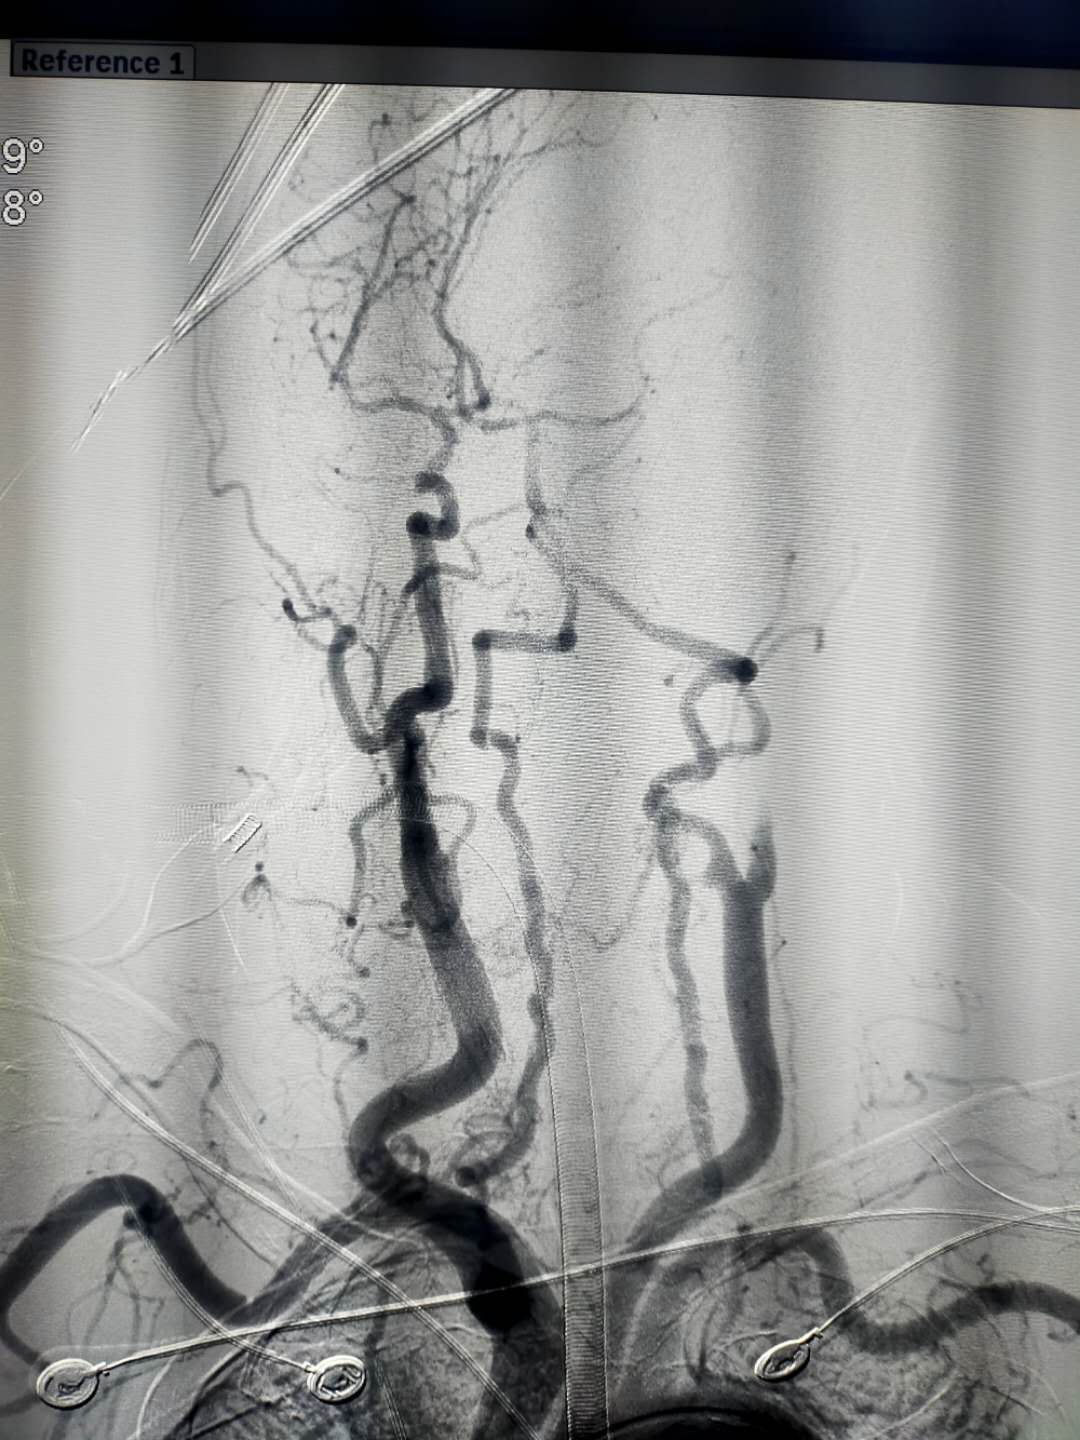

(抽吸后)

造影提示右侧颈总动脉起始部约3cm以上闭塞,立即送入椎动脉导管,插入闭塞血管近段抽吸血栓。

抽吸过程中,面临血管负荷大、血管迂回、抽吸困难、再次血栓形成等困难。定信心,绷紧弦、加把劲,面对难度系数100%的手术,王敏波团队坚定“咬定青山不放松、不破楼兰终不还”的信念,想尽一切办法抽吸血栓。

心往一处想,劲往一处使。在王敏波团队的努力下,历经2小时5分钟的奋战,7次抽吸,4次支架,难关终于被攻克。